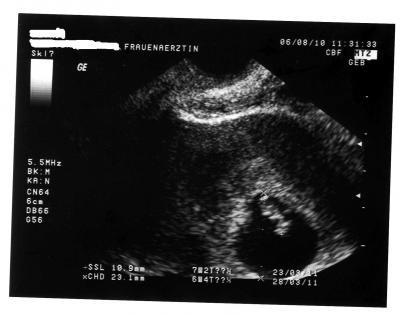

Hallo, heute war ich wieder zur FÄ, das Baby ist schon gut gewachsen, Herzchen schlägt prima, bin erstmal beruhigt. Hier mal ein Photo

Bild zu Krümelchen geht es gut - Forum für März - Mamis